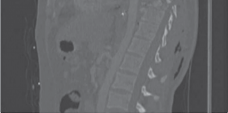

Figure 4.1 A thoracic flexion compression fracture with kyphosis.